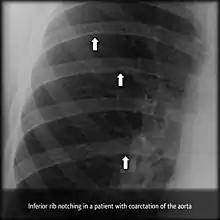

Notching of the ribs

Notching of the ribs (or rib notching) is a radiologic sign where the surface of the rib is deformed. It can be characterized as unilateral or bilateral, and should be differentiated between affecting the upper (superior) or lower (inferior) surface of the rib.

Inferior rib notching can be associated with aortic coarctation (as a result of dilatation of intercostal arteries[1]), superior vena caval obstruction, arteriovenous fistula, or following a Blalock Taussig shunt.